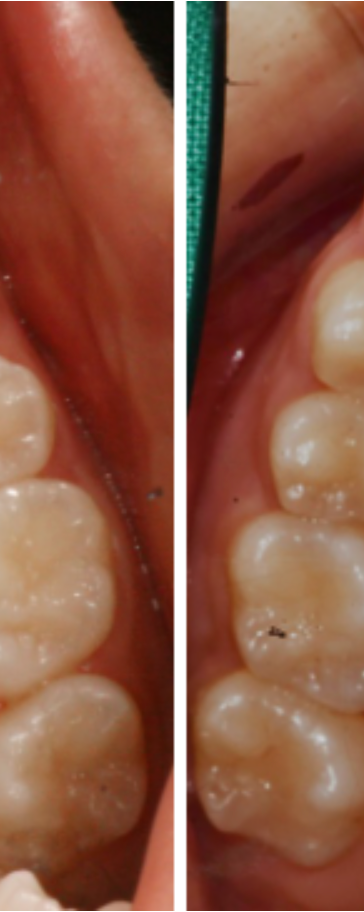

다음은 비발치교정 치료를

진행 한 후 촬영한 모습인데요.

작은 어금니를 발치하지 않은

상태에서 교정을 진행하게 되면,

위 사진에서 표시한 것과 같이

어금니를 포함한 모든 치아를

뒤쪽으로 이동시켜야 하기 때문에

어금니의 교합이나 위치에도

당연히 변화가 발생한다고 했어요.

이 과정에서 상, 하악니의 교합이나

치아 사이 간격을 적절하게

조절하지 못하게 되면 위,아래

어금니의 교합이 어긋나는 등의

부정적인 문제가 발생할 수 있는데요.